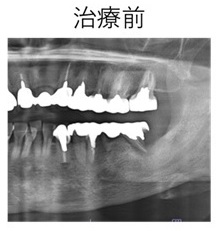

症例① 歯根破折のため左臼歯部を抜歯しインプラント治療を行なった治療例。